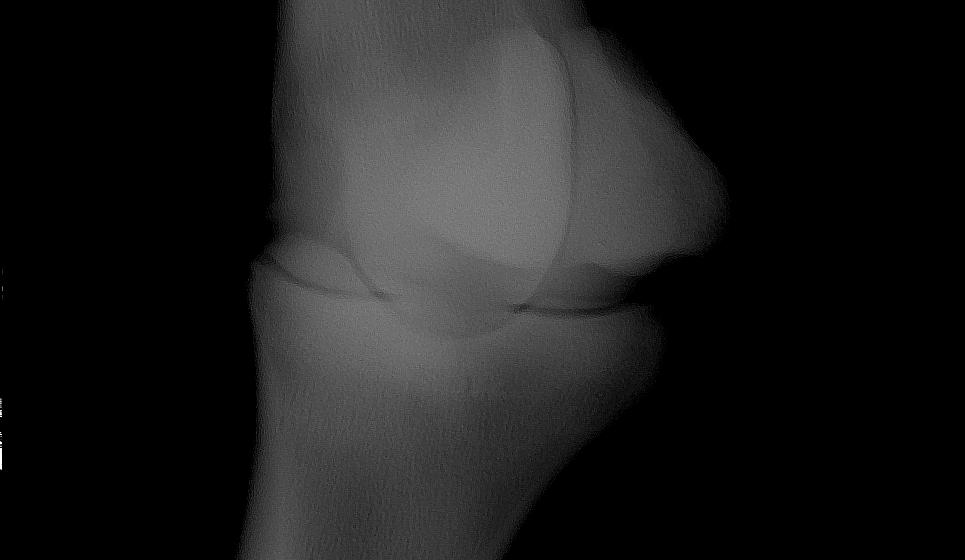

Thank you Christina and Dr. O. I finally have all the x-rays:

1) LF DLPMO

LF DLPMO

2) LF DMPLO

LF DMPLO

3) LF DP

LF DP

4) LF LAT

LF LAT

There is also a very mild osteophyte beginning on the proximal border of the phalanx in the LF DLPMO which suggests some sort of stress in the joint. It sounds like it is becoming unanimous from your end and considering this radiographic change I would not disagree with them.